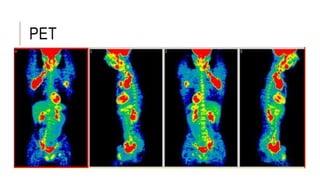

PET